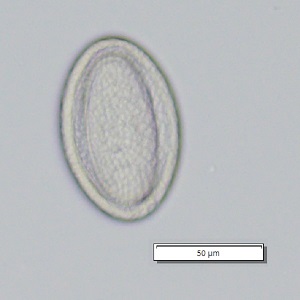

A 3-year-old boy was seen by a pediatrician for gastrointestinal pain and watery diarrhea. His parents conveyed that he has a propensity for putting insects in his mouth and sometimes eating them. A stool specimen was collected and processed for ova and parasites (O&P). A formalin-ethyl acetate (FEA) concentration was performed and a wet mount smear was prepared from the sediment and examined. Figures A and B show one parasite-like object at different focal planes at 200x magnification; another object from the sample is shown in Figures C and D, also at different focal planes, at 200x magnification. What is your diagnosis? Based on what criteria?

Figure A